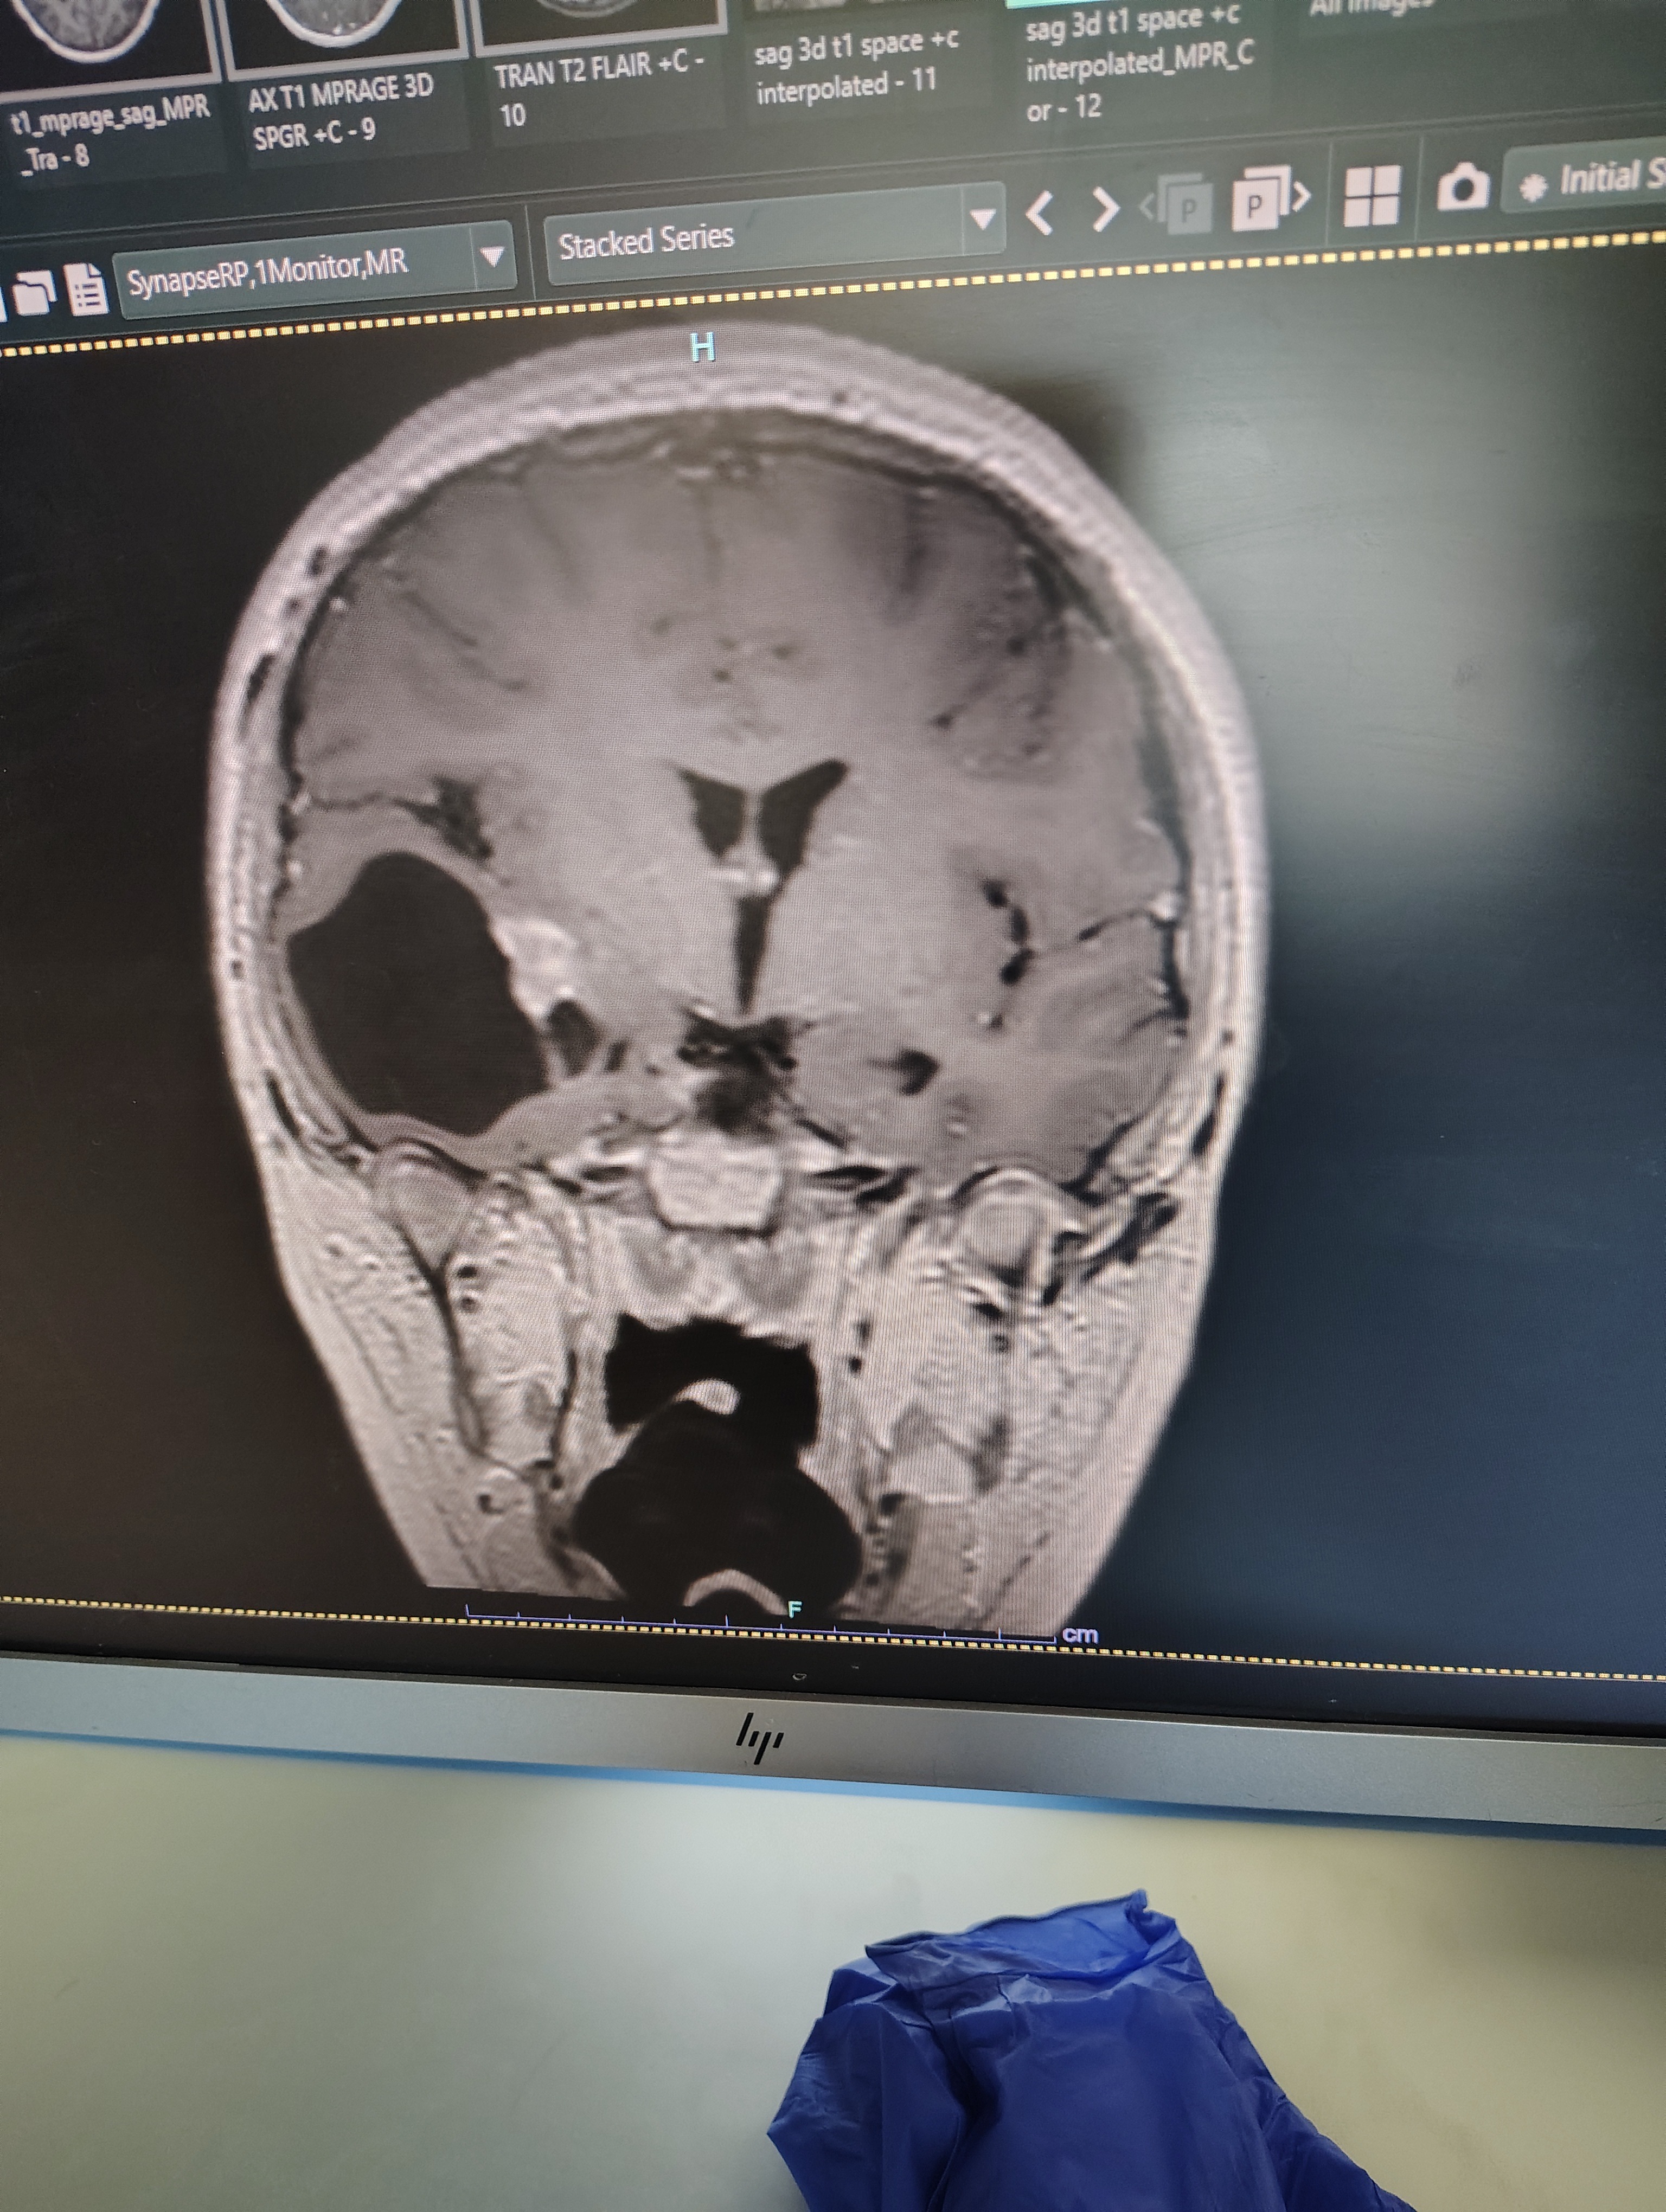

Our son went in for surgery on Thursday November 13th due to a tumor & cyst that was in his brain. The tumor was benign & the Dr was able to completely drain the cyst & remove the tumor.